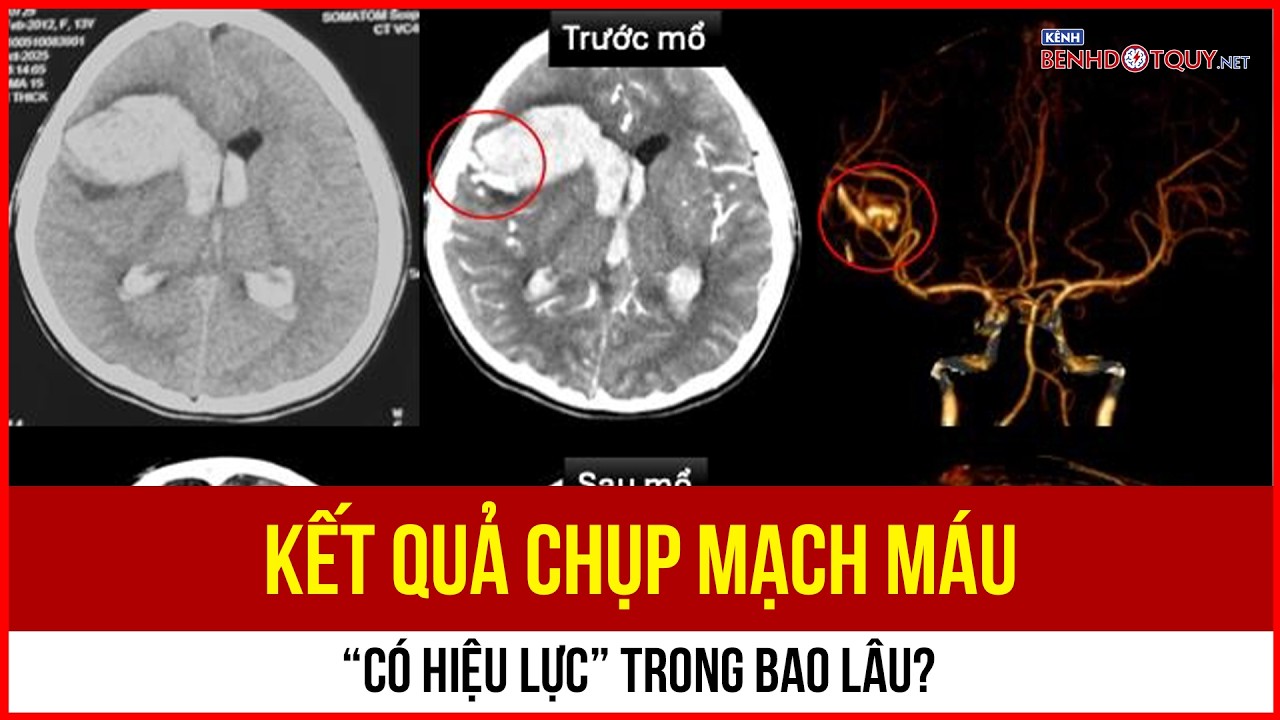

Hình ảnh DSA cho thấy, bệnh nhân bị dị dạng mạch máu tủy cổ gây yếu liệt tứ chi

Hình ảnh DSA cho thấy, bệnh nhân bị dị dạng mạch máu tủy cổ gây yếu liệt tứ chi

Kết quả chụp DSA cho thấy anh Đ. bị dị dạng mạch máu tủy vùng cổ ngang mức C5 -C7 cấp máu từ các nhánh tủy trước, tủy sau 2 bên và một nhánh của động mạch thân giáp cổ phải.